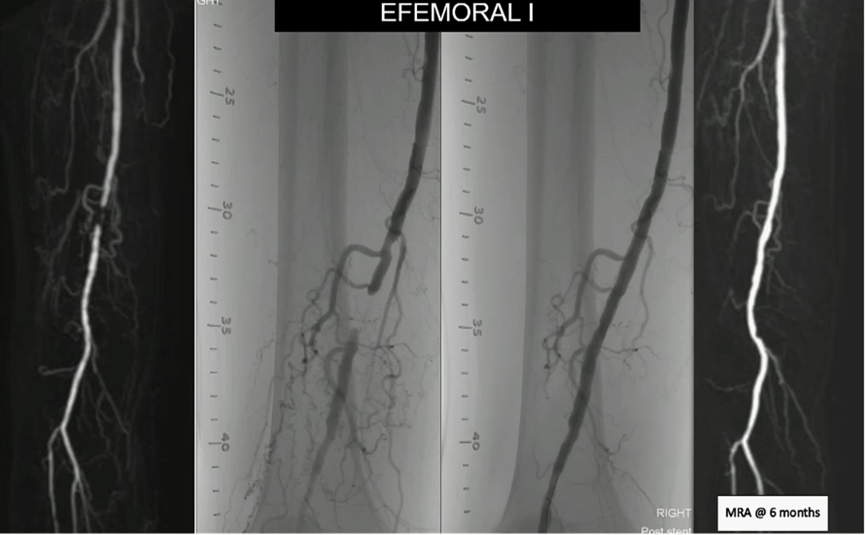

EfemoralⅠ临床研究

纳入100名有症状的外周动脉疾病患者(卢瑟福分级2~4级),为股腘动脉单个粥样硬化性原发狭窄或闭塞。该研究为前瞻性、单臂、多中心研究;5.5 mm≤RVD≤6.5 mm,病变长度≤90 mm;单个靶病变接受单个Efemoral BVS治疗。目前,临床研究仍在进行中。

临床终点包括卢瑟福分级(RB)和临床驱动靶病变血运重建(CD-TLR)。

定量影像终点包括多普勒测量收缩期峰值流速的比值、血管造影测量支架内/节段内晚期管腔丢失和直径狭窄率。